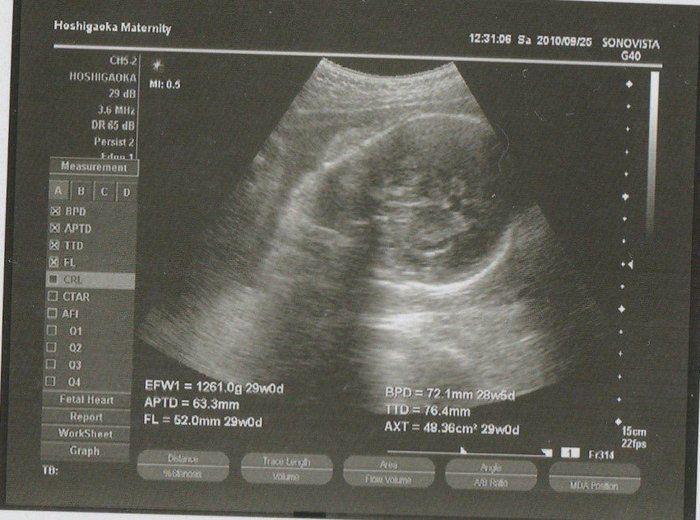

水野谷つむぎさんの妊娠32週目のエコー写真 赤ちゃんの推定体重2080g

宝物の息子とはおなかのなかで対面してた!エコー写真で出会いからこれまでを振り返る

この頃になると股関節痛が酷くなりました。少し歩いただけで、普通には歩けない状態になってしまい、道端でストレッチをしてしのいでいました。